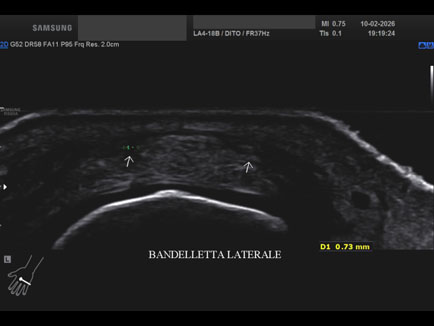

Data inserimento: 13/02/2026

Ecografia del: 10/02/2026

Strumento: Samsung

Sonda: Lineare

Commento all'esame: rottura della bandelletta laterale MTC-F del II° dito con conseguente lussazione del tendine estensore.

Conclusioni: rottura della bandelletta laterale metacarpo-falangea del 2° dito della mano sinistra (tear of the lateral band of the metacarpophalangeal - MCP - joint of the left index finger).